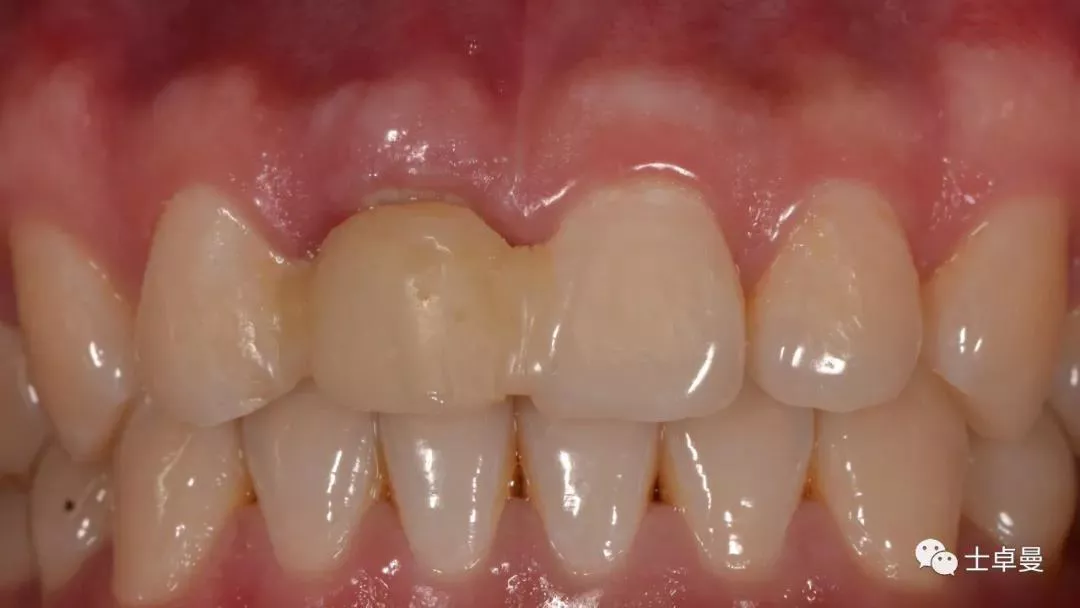

临时修复后2个月,龈缘及龈乳头位置理想,软组织健康

· 2个月后,见唇侧骨弓轮廓可,龈缘及龈乳头形态自然,去11临时修复体,植体ISQ值测定82,个性化取模,试戴Variobase氧化锆基台+LAVA氧化锆单冠,就位被动性良好,增加基台扭力至35Ncm,粘接固位上部冠,调合抛光。

永久修复前穿龈袖口健康

完成永久修复,骨弓轮廓、龈缘及龈乳头形态自然,可见牙龈点彩,修复体外形及色泽可,患者满意。

X线示,永久修复体已就位